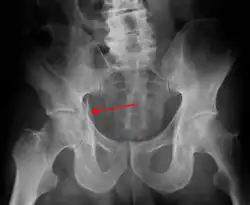

Fractures of the acetabulum occur when the head of the femur is driven into the pelvis. This injury is caused by a blow to either the side or front of the knee and often occurs as a dashboard injury accompanied by a fracture of the femur.[1]

To understand the fracture pattern of a fractured acetabulum, it is essential to have minimum three x-ray views, though use of CT scan with 3-D reconstruction of images has made understanding of these fractures easier.

- Pelvis with both hips antero posterior view. This view shows six important landmarks of the acetabulum, specifically:

- Weight bearing dome

Ideal x-ray visualization of an elementary fracture will depend on the fracture type: